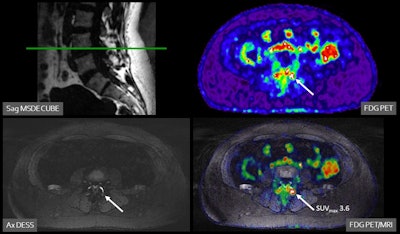

The researchers split the participants into two groups, a control arm (n = 14) consisting of standard clinical care without F-18 FDG PET/MRI or an intervention arm (n = 13; 6 LBP patients and 7 THR patients) who underwent the hybrid scans and subsequent clinical management. Potential pain generators were identified by increased F-18 FDG radiotracer uptake on PET combined with anatomical abnormalities on MRI.

A 47-year-old female patient with chronic pain in the left lower back/buttock with unknown cause. PET demonstrated focally increased FDG uptake at the left facet L3-4 l. MRI shows minimal fluid, but no edema. Follow-up PET-MRI after six months shows a similar pattern. The patient is on the waiting list for targeted facet joint infiltration (typically not covered by insurance in the Netherlands).Image courtesy of Marijn Mostert

According to the findings, PET/MRI provided new diagnostic insights into the potential pain generator in 12 patients (86%). Moreover, the findings were discussed with the referring physicians, which led to multiple changes in clinical management. Two patients subsequently underwent lumbar nerve root injection, one patient was referred for facet joint injection, and one patient underwent surgical discectomy.